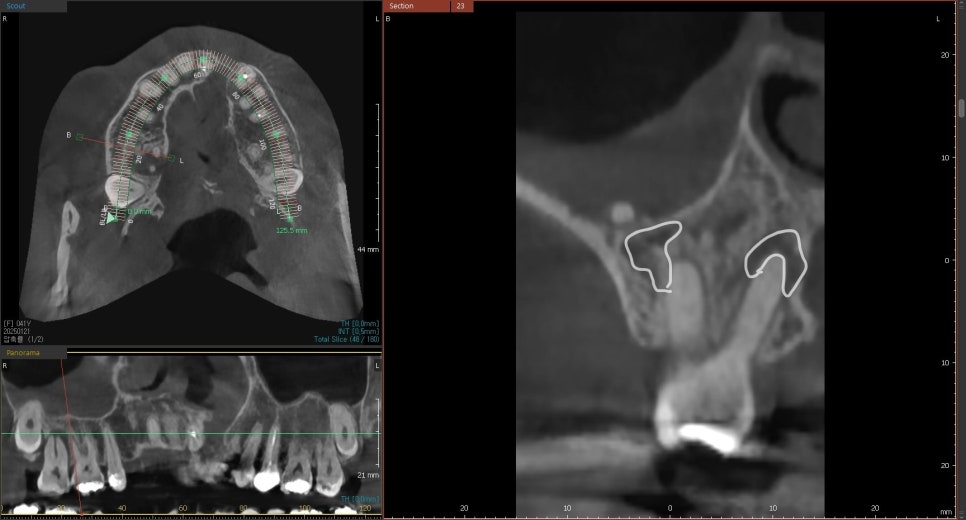

조금 더 정밀한 사진 촬영을 해 보니 (ct) 상황은

예상보다 심각했습니다.

뿌리 사이에 염증이 깊숙이 퍼져 있었고,

치아를 지탱하는 주변 뼈가 이미 상당 부분 손실된 상태였습니다.

게다가 입천장의 절반 이상이 심하게 부어올랐고,

잇몸에서는 고름이 나오고 있었습니다.